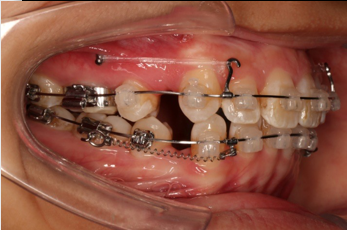

IntraoralExamination(2016-08.31,Wu)

• 磨牙,尖牙I类关系,中线齐

• 上下牙列中度拥挤

• 上下前牙唇倾

2018.11.14  术后磨牙尖牙I类关系,中线齐,覆合,覆盖正常